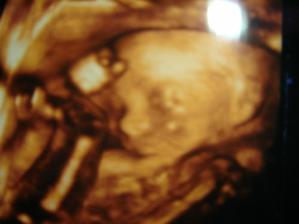

1/12/08: byli jsme na 3D ultrazvuku, miminko už nebylo tak klidné jako na předchozích UTZ, nedalo se pomalu ani zachytit, ale bude to prý z 95% holčička, máme radost!!!!!!!!! Je to pěkná čahounka (asi po mně🙂)), měří 20cm, váží 215g.

5/1/09 : 3D UTZ, opět potvrzena holčička, vážíme 510g. a měříme 25 cm.